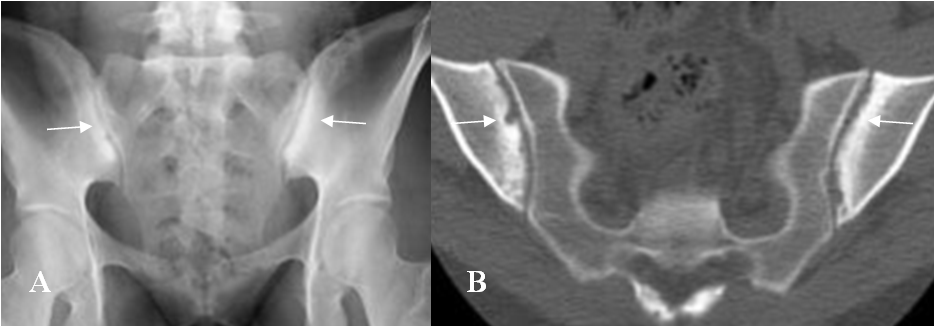

Fig 57 B. Espondilitis anquilosante.

A: Rx AP y B: TAC axial. Esclerosis y erosión de los componentes iliacos, de ambas articulaciones, por espondilitis anquilosante.

Fig 57 C. Espondilitis anquilosante.

A: Rx AP y B: TAC axial. Fusión de la articulación sacroiliaca derecha y disminución del espacio y esclerosis de la izquierda, por espondilitis anquilosante.